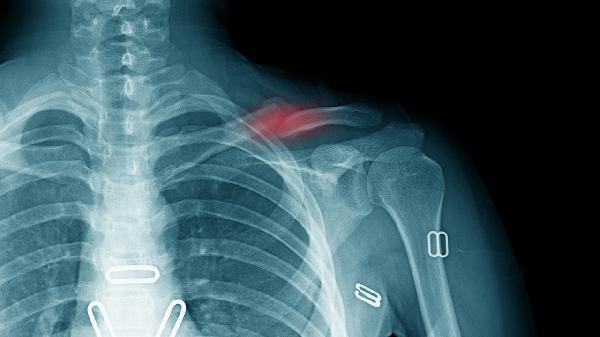

锁骨骨折后若固定不牢固或过早活动,可能影响骨折愈合,导致骨不连。骨不连表现为局部持续疼痛、异常活动,X线检查可见骨折线清晰无愈合迹象。此时需手术清除纤维组织并重新固定,配合植骨促进愈合。术后需严格制动,避免二次损伤。